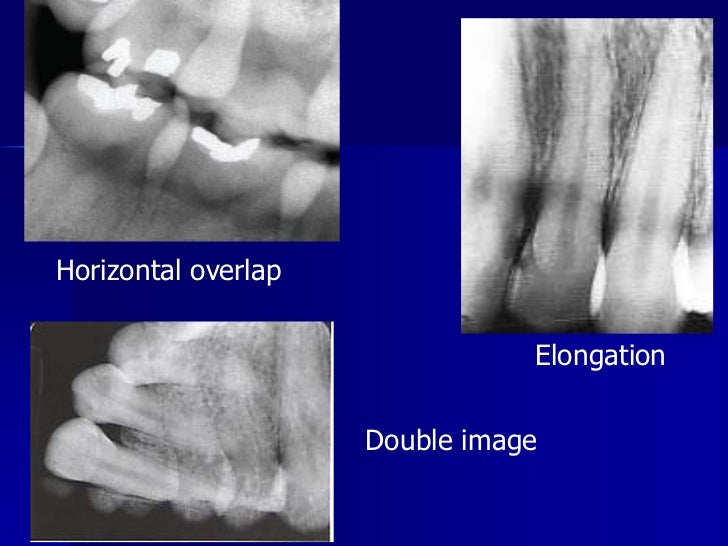

Radiographic errors and artifacts Radiographic Errors In Dentistry Pdf errors and artefacts in dentomaxillofacial include positioning errors in intraoral techniques, panoramic. Reasons of appearance of technical errors and artefacts in. radiographic errors may be due to technical errors [ errors related to the technique of taking the. technical errors and artefacts in dental radiography. in dentistry, the most common test ordered in a preliminary examination. Radiographic Errors In Dentistry Pdf.